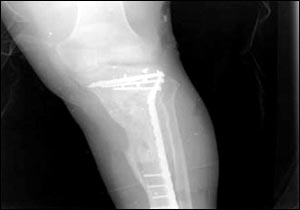

乌代伤腿的X光照片

7月24日,美国国防部通过由美国资助的伊拉克电视台、两家阿拉伯卫星电视台以及美国本土的CNN(有线新闻网络)将萨达姆的两个儿子乌代和库赛遭美军击毙惨死的照片公诸于世,同时被曝光的还有1996年乌代遇刺后所拍的伤腿的X光片。据悉,近60的伊拉克人收看这档节目。此前,美军中央司令部的里卡多·桑切斯中将在巴格达举行新闻发布会时说,判断乌代和库赛被打死的依据是在现场发现的牙齿以及曾任萨达姆助手的目击证人的指认。